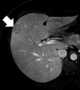

Liver lesion with central scar